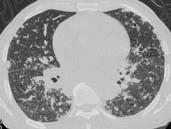

问题 男,38岁,咳嗽,咳痰,关节疼痛,外周淋巴结肿大,结合CT图像,最可能的诊断是 ( )

选项 A.肺泡蛋白沉积症 B.肺间质病 C.结节病 D.肺结核 E.霍奇金病

答案 C